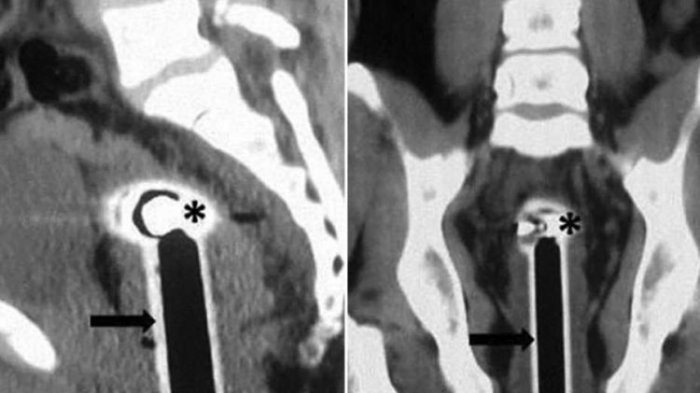

Ia membantah sengaja memasukkan kepala selang sendiri. Dalam keterangan laporan dokter di jurnal BMJ, tanda-tanda vital stabil dan tidak ada pendarahan di rektum atau organ terakhir usus besar.Dari hasil pemindaian, kepala selang itu berada di panggulnya.